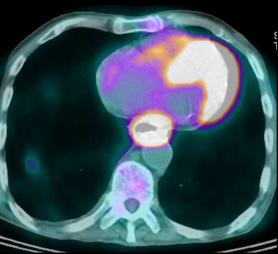

- Bilan d'extention du meme cas en Pet

/CT : Image tres net du tumeure de oesophage 1/3

moyen avec metastase ganglionaire, du foie ,

reins , ganglion pelviene et des os

|